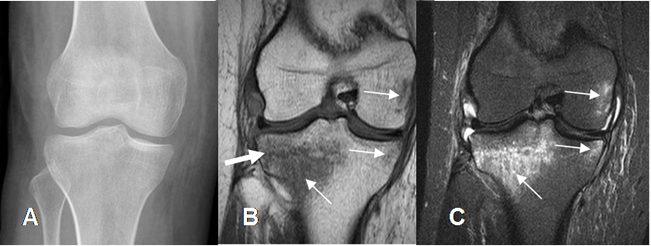

Fig 22. Edema óseo traumático.

A: Rx AP, sin cambios patológicos.

B: RM coronal en T1 y C: RM coronal en STIR. Zonas de edema óseo post-traumático, hipointensas en T1 e hiperintensas en STIR. (Flechas delgadas). Adicionalmente hay imagen hipointensa y en sentido horizontal, en T1, que corresponde a fractura lineal (Flecha gruesa).